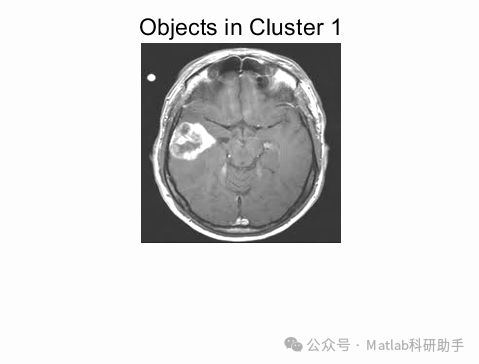

⛳️ 运行结果